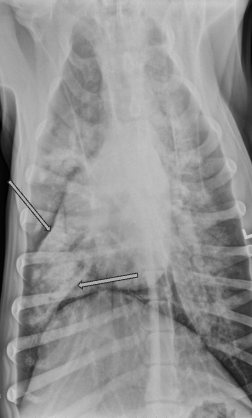

What lung pattern? What are the arrows pointing to?

Bronchial pattern

tram tracks